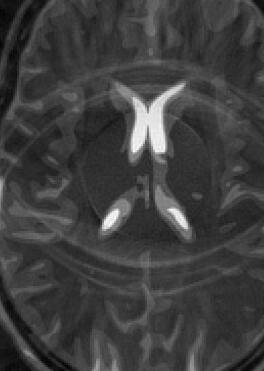

Fig. 14 exhibits the reconstruction results with the spiral trajectory with for . The reconstructed images are displayed alongside profile plots of row . The same is also presented in Figures 13 for .

When sampling on a spiral trajectory, SPURS further demonstrates its superior performance over the other methods. For values high enough, SPURS, NUFFT and rBURS with achieve very good results, but the performance curve for each method levels off for different values of (Figures 9, 10, 11 and 12). Iterative SPURS levels off for values as low as , requiring about iterations to converge to its best result. For these low values, significant artifacts appear in the reconstructed image produced by all methods excluding SPURS as presented in Fig. 13 for and Fig. 14 for . The performance curve of the NUFFT method and of a single iteration of SPURS level off at around . For and higher, a single iteration of SPURS produces marginally better results than those produced by NUFFT, which requires about iterations to converge. Among the other non-iterative methods, both rBURS with and convolutional gridding perform similarly well for , however the results are still inferior to those of a single iteration of SPURS, all of which have similar computational complexity.